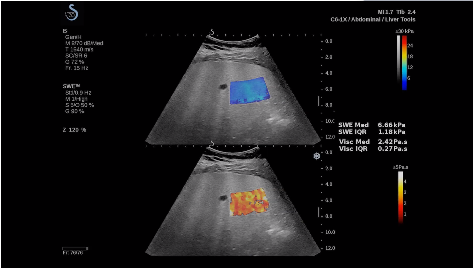

法國聲科影像(SuperSonic Imagine,SSI. Euroniex:FR0010526814)近日發(fā)表公告,宣布其研發(fā)的新一代“極速”超聲成像平臺(UltraFast Imaging),首次實現(xiàn)了肝臟的多項超聲定量評估新指標同步檢測,包括:Att PLUS,SSp PLUS和Vi PLUS等,基本涵蓋肝臟相關(guān)病理變化指征的如纖維化、脂肪變、炎癥等。據(jù)悉,此多項新技術(shù)新將搭載于新Aixplorer系列E超系統(tǒng)。

E超相關(guān)技術(shù)已被多項多中心大樣本研究證實對于肝纖維化無創(chuàng)評估有重要意義,同時也可全面應(yīng)用于乳腺、甲狀腺、肝臟、前列腺、肌骨、婦科等全身各組織器官的定量評估和鑒別診斷。在慢性肝臟方面,聲科E超的肝臟相關(guān)定量診斷技術(shù)集,于2018年獲得美國FDA認證,成為FDA歷史上首次獲批的單病種超聲全面定量解決方案。